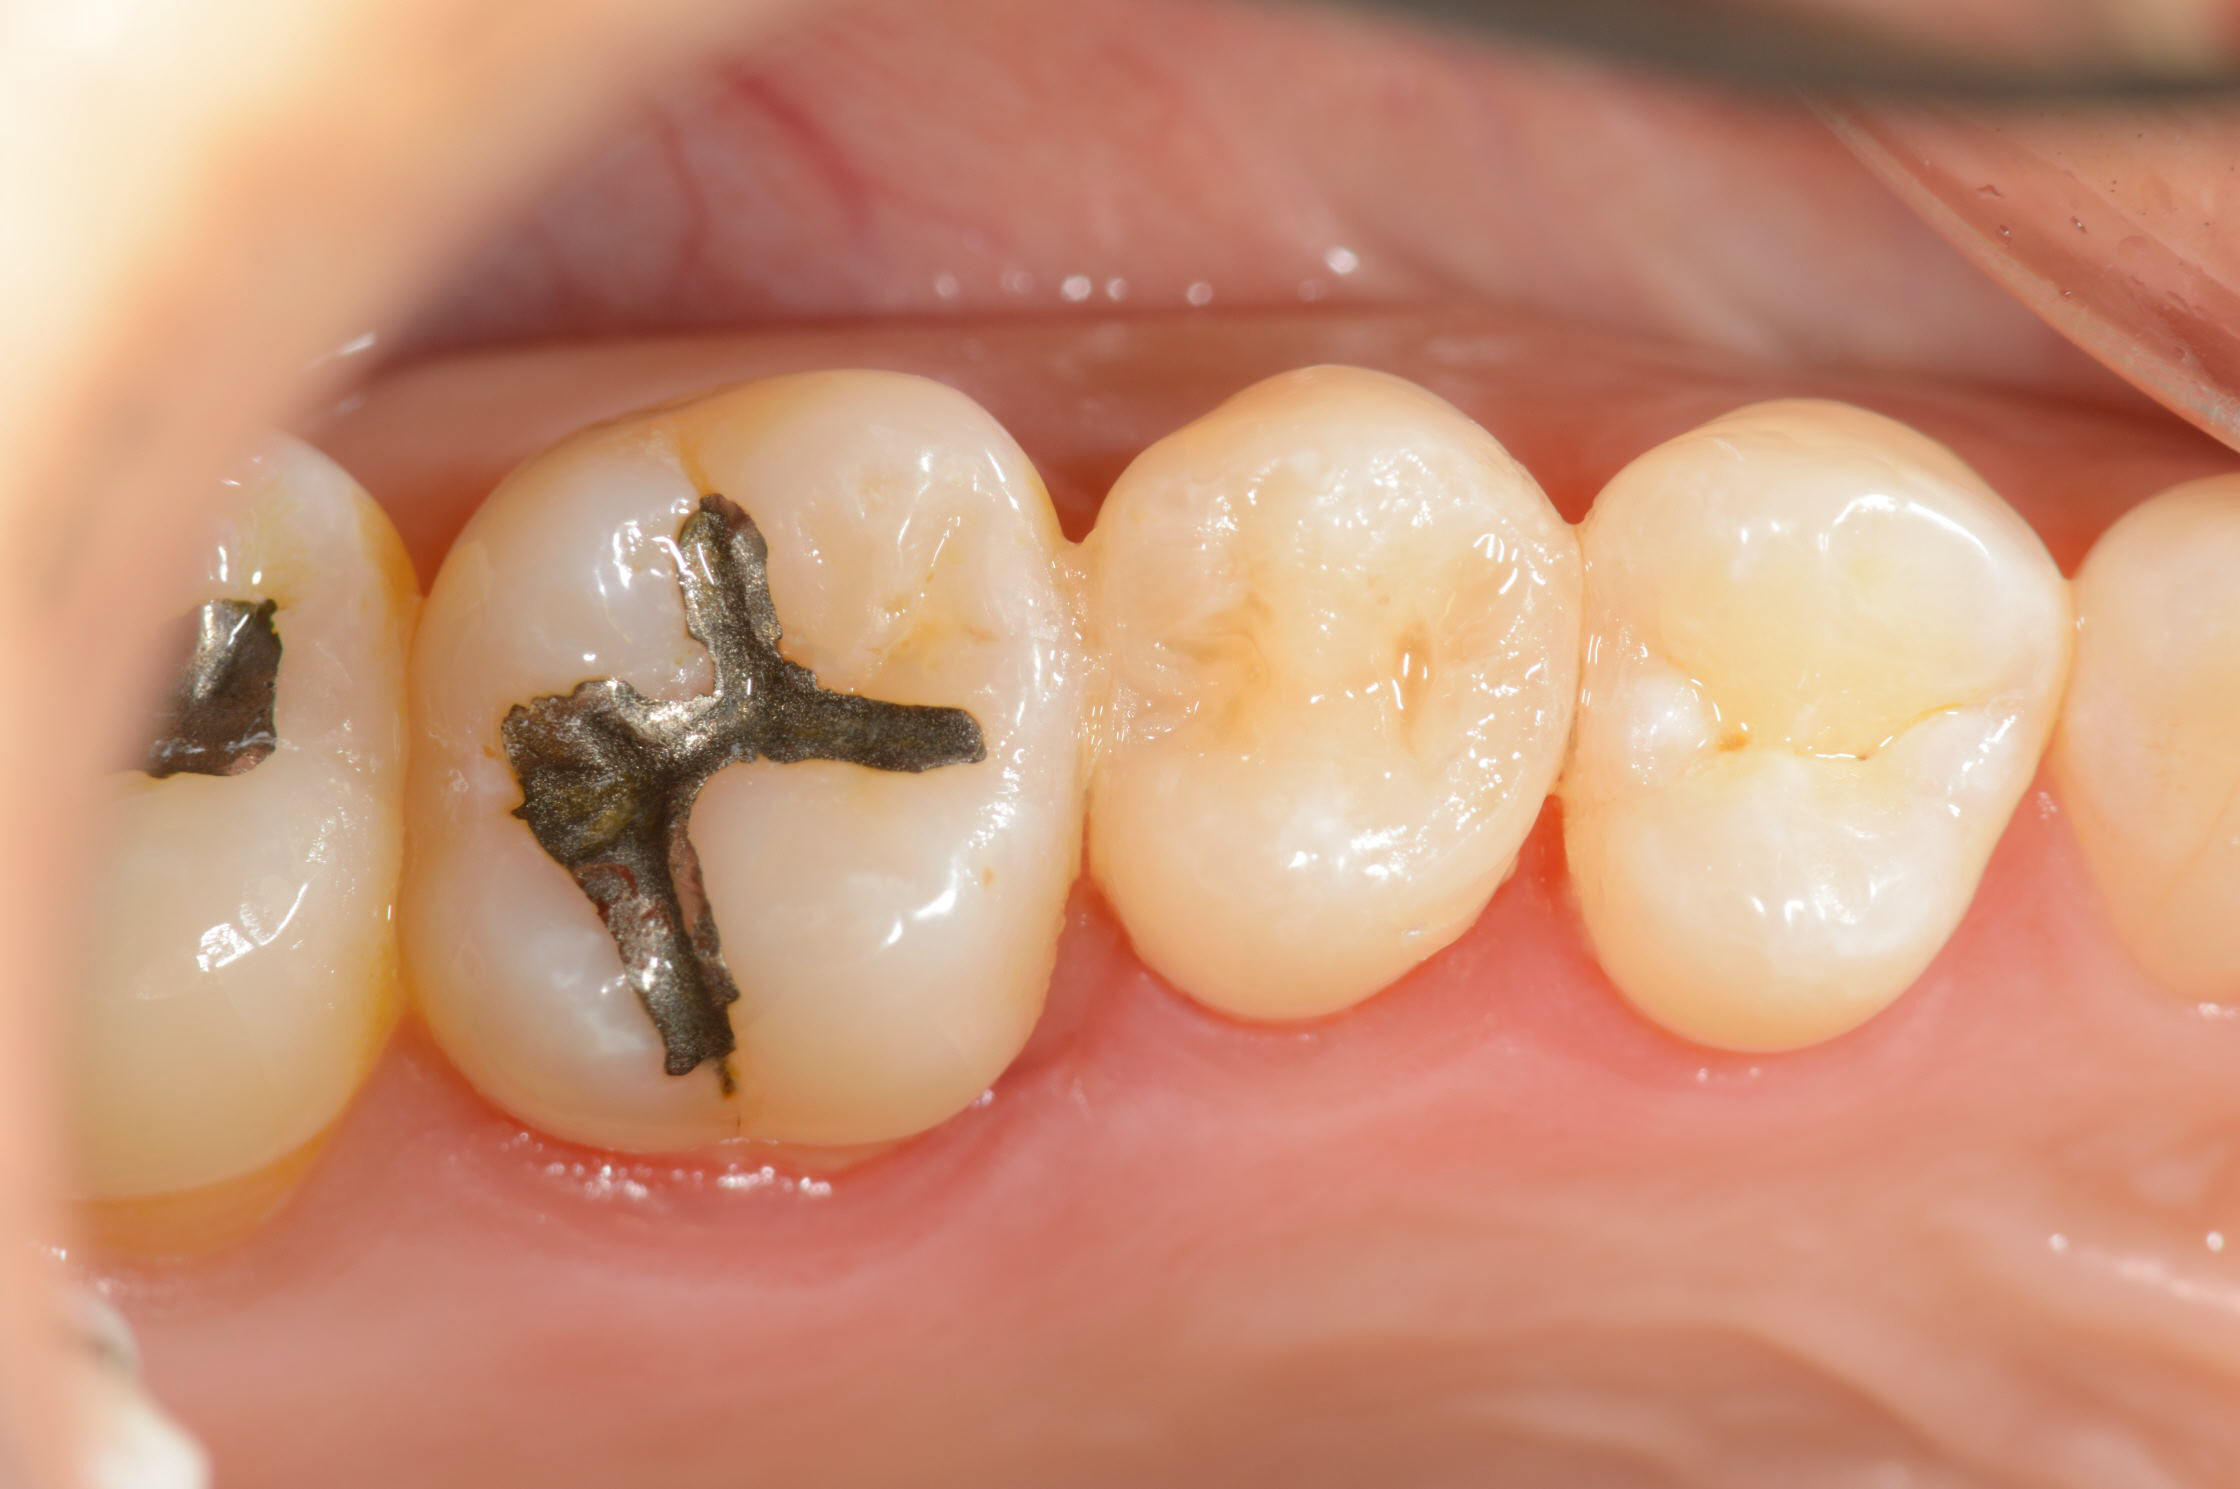

6〜7年前に治療した右上の歯が、噛むと痛むとのことで来院されました。細かく診査したところ、歯の一部に圧痛があり、マイクロスコープで拡大して確認したところ、詰め物に細かなヒビが認められました。

痛みのある部分を慎重に確認したところ、以前に装着された詰め物が割れていることが確定しました。